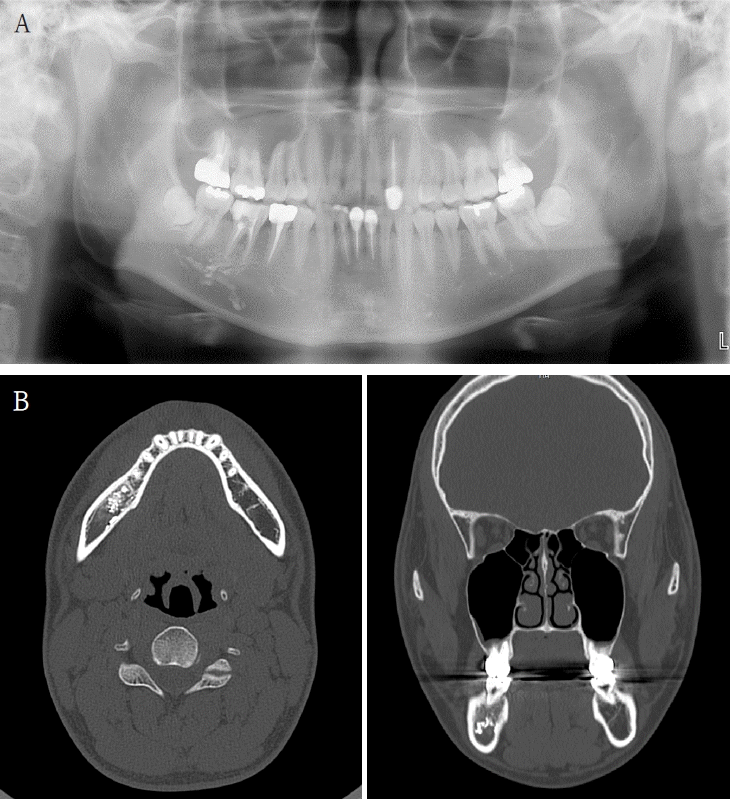

A 41-year-old female reported persistent numbness in the right lower lip and chin following endodontic treatment of the mandibular right second molar (#47). A panoramic radiograph and CBCT revealed extrusion of Calcipex II into the IAN (Fig. 3). She declined surgical intervention and was treated conservatively with mecobalamin and gabapentin. Serial follow-ups at one and three months showed no clinical improvement.- Case 3